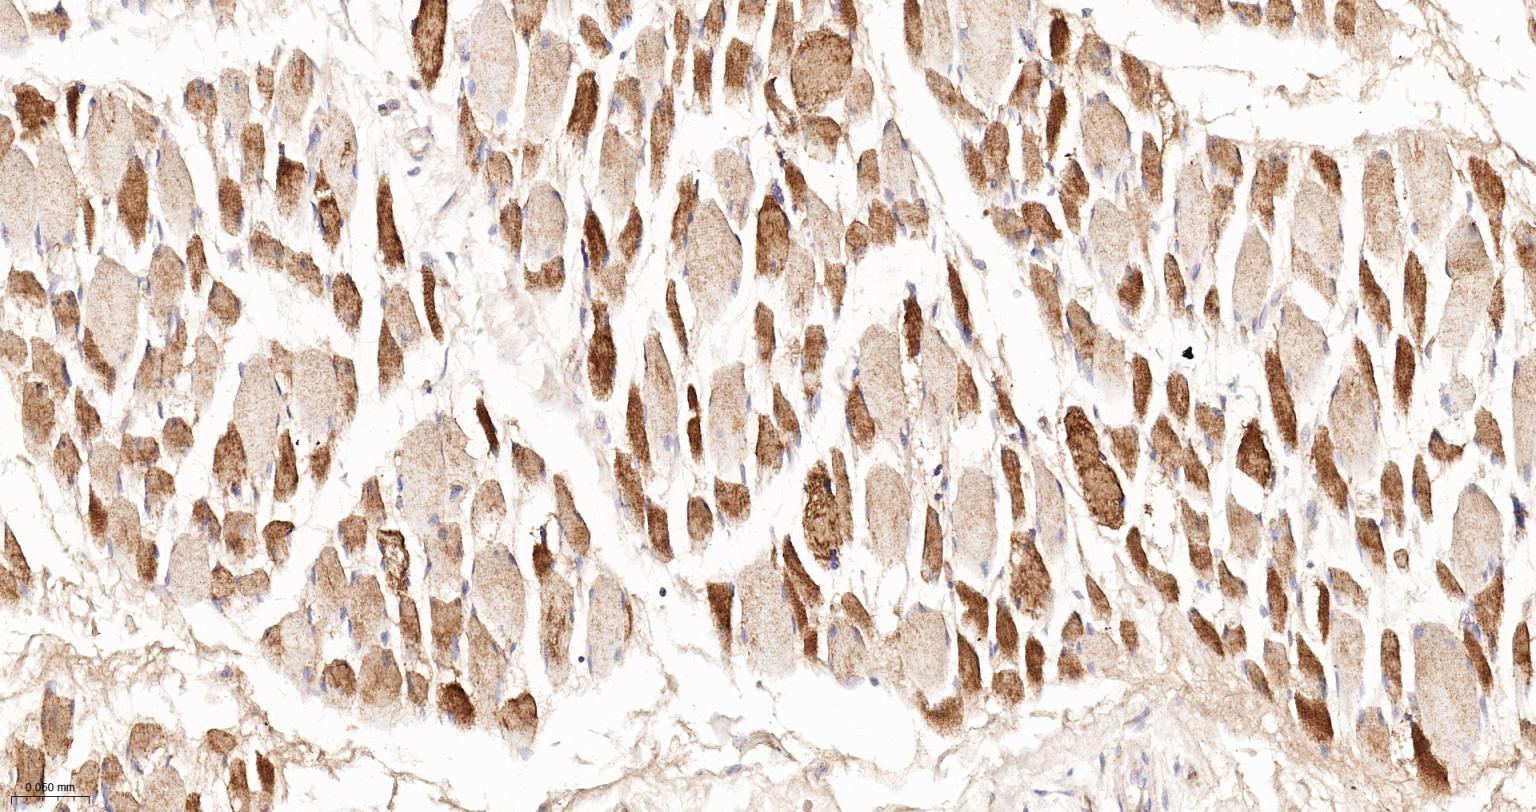

Paraformaldehyde-fixed, paraffin embedded Human Skeletal muscle; Antigen retrieval by boiling in sodium citrate buffer (pH6.0) for 15 min; The section was incubated with TSC1 Monoclonal Antibody, Unconjugated (bsm-62173R) at 1:200 overnight at 4°C, followed by conjugation to the bs-0295G-HRP and DAB (C-0010) staining.